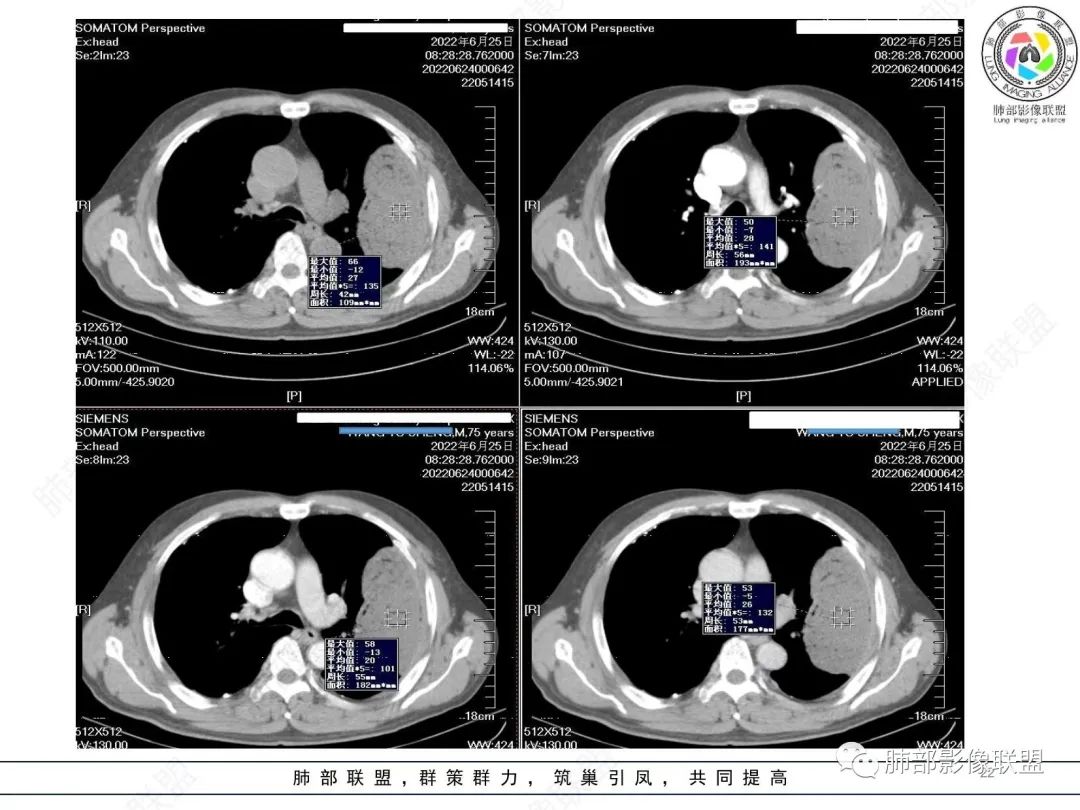

左肺上叶大肿块,膨胀性生长,边界清,密度较低,见部分坏死区,强化弱,肿块见支气管充气V扩张征,分布僵直,枯树枝特点,另一个重要特点血管造影征,淋巴瘤,肿块长轴与胸膜平行,与隐球菌鉴别,隐球荚膜抗原检查,明确诊断经皮肺穿刺。另胸膜钙化(问诊既往有无患胸膜炎病史)。

老年男性,糖尿病病史,消瘦、乏力三个月,影像表现左肺上叶胸膜下团块,有一定张力,内部疏松,可见支气管影及坏死区,增强病灶边缘环形强化,内部未见强化,考虑炎性肉芽肿病变,隐球?奴卡?放线菌?鉴别淋巴瘤。

左肺上叶胸膜下肿块,宽基底与胸膜相连,跨叶裂,边缘清晰膨隆,其内支气管充气,部分扩张、僵直,无明显强化,血管造影征,考虑淋巴瘤,鉴别腺癌

左肺胸膜下巨大占位,跨叶裂,宽基底与胸膜相连,胸膜钙化,平扫密度较低,强化不明显,可见内部血管显影,支气管充气征和扩张,考虑为恶性,倾向于淋巴瘤

左侧胸腔巨大肿块,跨叶生长,临近胸膜钙化,边缘模糊,可见支气管影,定位肺内,增强后轻度强化,边缘见血管影,考虑淋巴瘤,鉴别肉瘤

左肺上叶胸膜下肿块,膨胀性生长,边界清晰,密度不均部分坏死,未见强化,病灶内支气管迂曲扩张,病灶长轴与胸膜平行,胸膜下脂肪间隙存在,胸膜钙化,考虑放线菌?毛霉?鉴别淋巴瘤

支持淋巴瘤,左上肺大肿块,有分叶,边缘光整,病灶内密度不均,可见支气管扩张征,增强后可见血管影征。周围肺野清晰。

左肺上叶肿块,宽基底与胸膜相连,跨叶裂,边缘清晰膨隆,可见小分叶,其内支气管充气,部分扩张、僵直,呈枯枝征,支气管达边征,增强无明显强化,可见血管造影征,考虑恶性病变,淋巴瘤,鉴别粘液腺癌。

4)密度:肿块平扫为软组织密度,由于体积较大,内部常见大片状坏死,可出现不规则厚壁空洞或坏死内多发无壁小空洞,坏死多不均匀:坏死灶内可见如柳絮样的斑片样强化灶,坏死边缘与非坏死区分界不清本例坏死较明显,密度不均匀。

5)肿瘤强化方式:肺部恶性肿瘤强化程度与其血供丰富程度相关,血供丰富多强化明显,反之则较差。由于PSC 周边实性部分富血供及内部黏液变性、坏死,增强后肿块多数呈轻-中度边缘环形强化或不均匀小斑片状强化。国外学者对照病理发现肿瘤细胞或胶原组织增强扫描时强化,无强化的低密度区代表了黏液样变性区和出血坏死区。